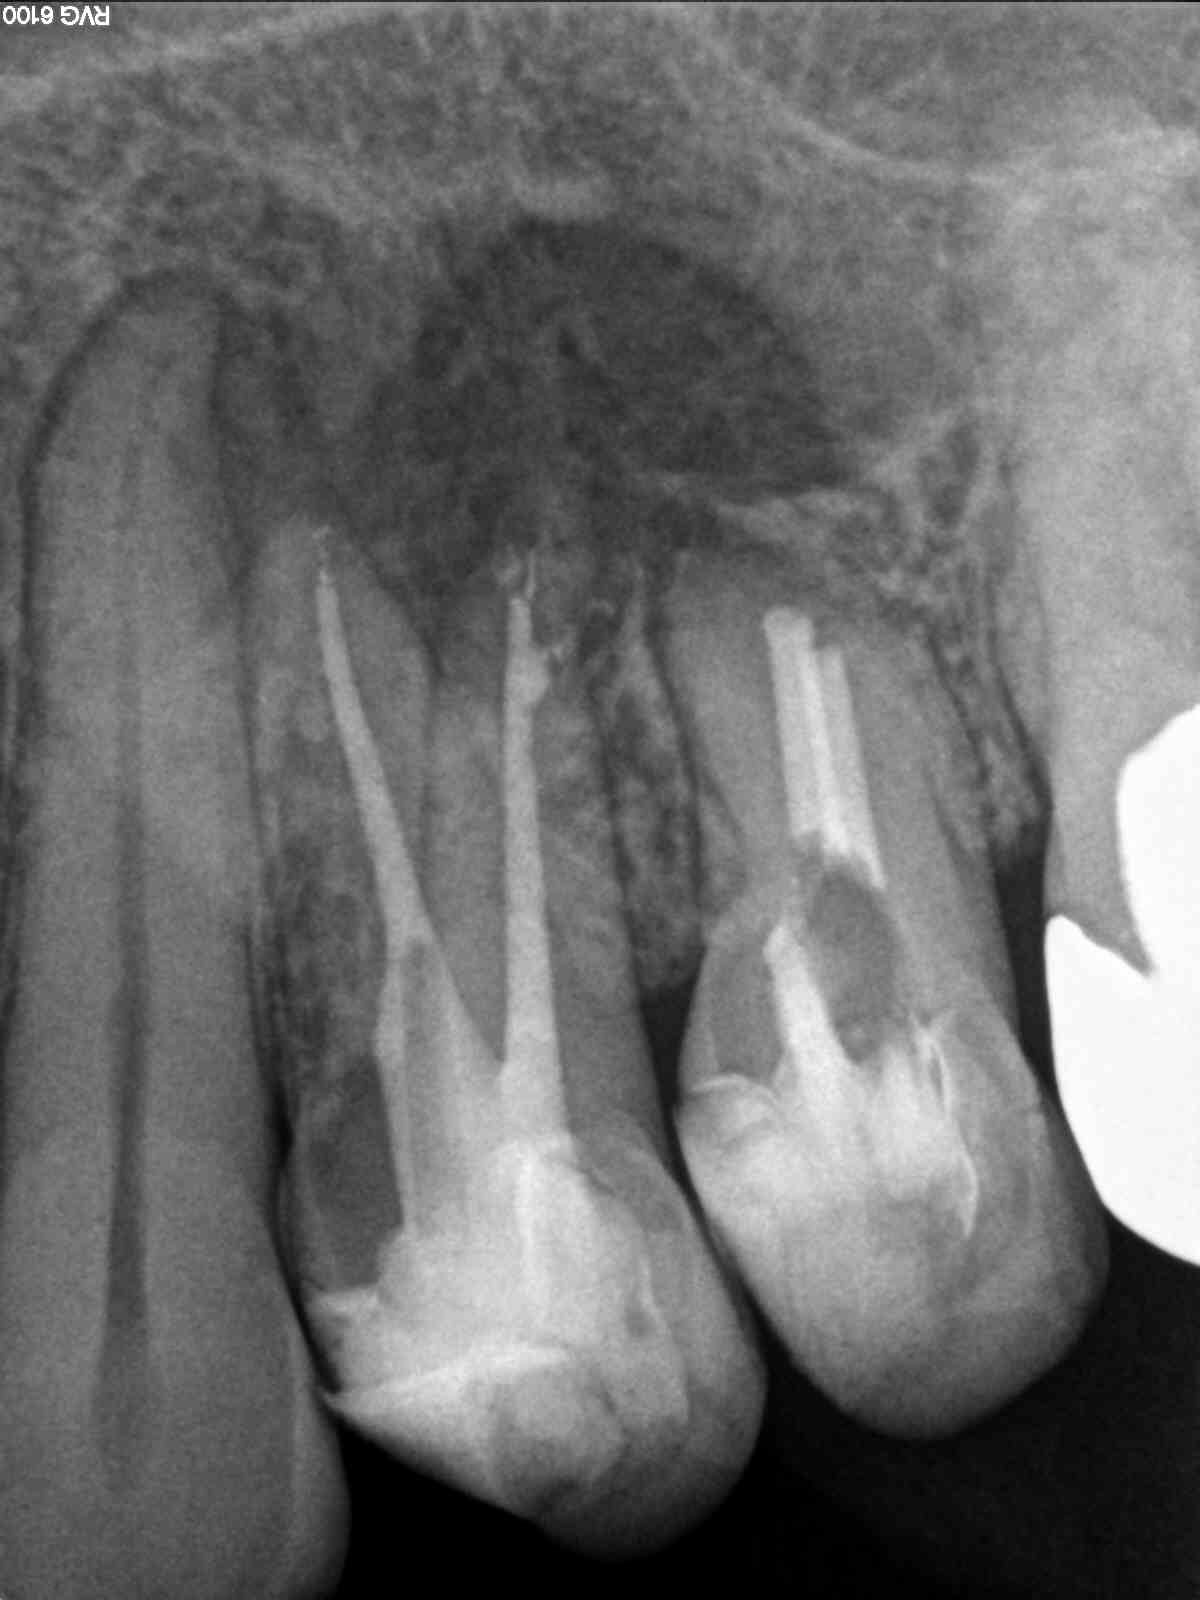

R7

1200 × 1600

Große Aufhellung, langes Recall